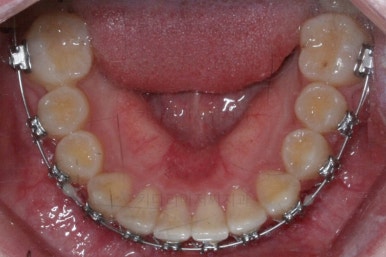

치아는 매우 가지런해졌고 뾰족하던 앞니의 형태도 좋아졌어요.

매복되어 있던 송곳니도 잘 나왔고 과개교합도 물론 개선이 되었습니다.

임시 개념으로 치아 사이즈를 키운건데 환자분은 만족하시나봐요.

보통 올세라믹, 라미네이트 등 보철치료는 성인이 되어서 해야해서 이래나 저래나 이정도에서 만족하기로 했습니다.